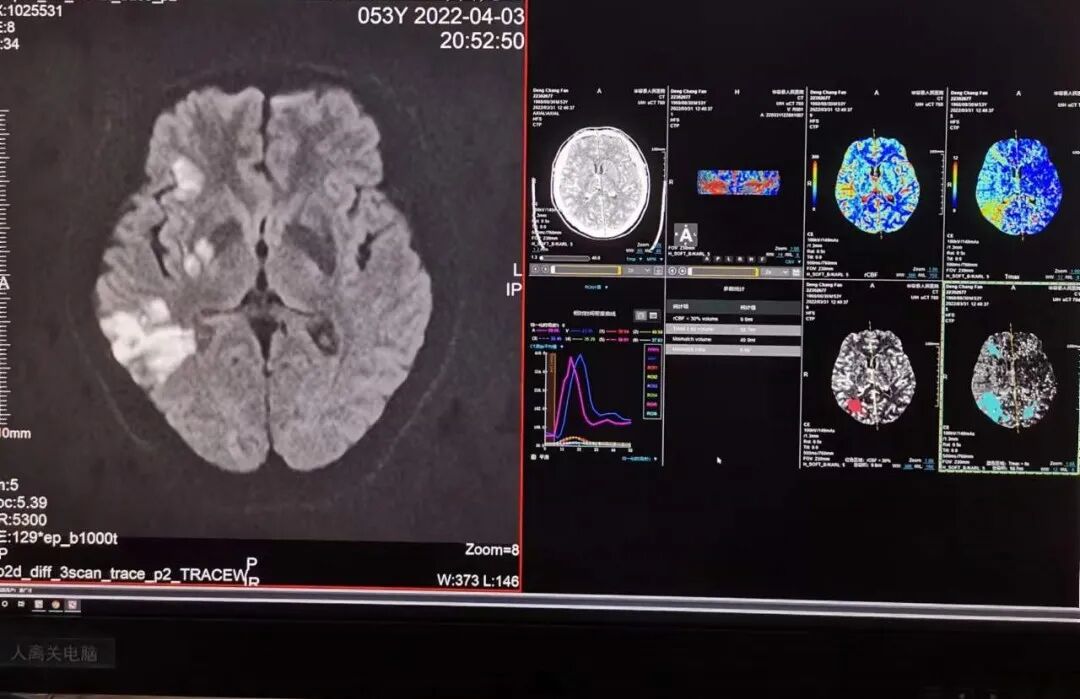

新设备的引进让我们又多了一项新技术--“CT脑灌注成像”。CT脑灌注成像是对选定层面进行连续动态扫描,获得所选层面的每一像素的时间密度曲线,并通过数学模型处理得到脑血容量、脑血流量、对比剂平均通过时间、对比剂达峰值时间等血流动力学参数和灌注图像表现,能有效评价脑组织的灌注状态,能更有效并量化反应局部脑组织血流灌注的改变,是一种CT应用领域的前沿科技,对明确病灶的血液供应具有重要意义。

它可以早于核磁共振弥散加权像(DWI)发现脑梗死,可以发现DWI不能发现的脑梗死前期脑组织局部缺血区及生理学改变,明确区分缺血半暗带,有利于溶栓和预后的判断,也是目前公认的对缺血半暗带能做出的最科学的评估方法。